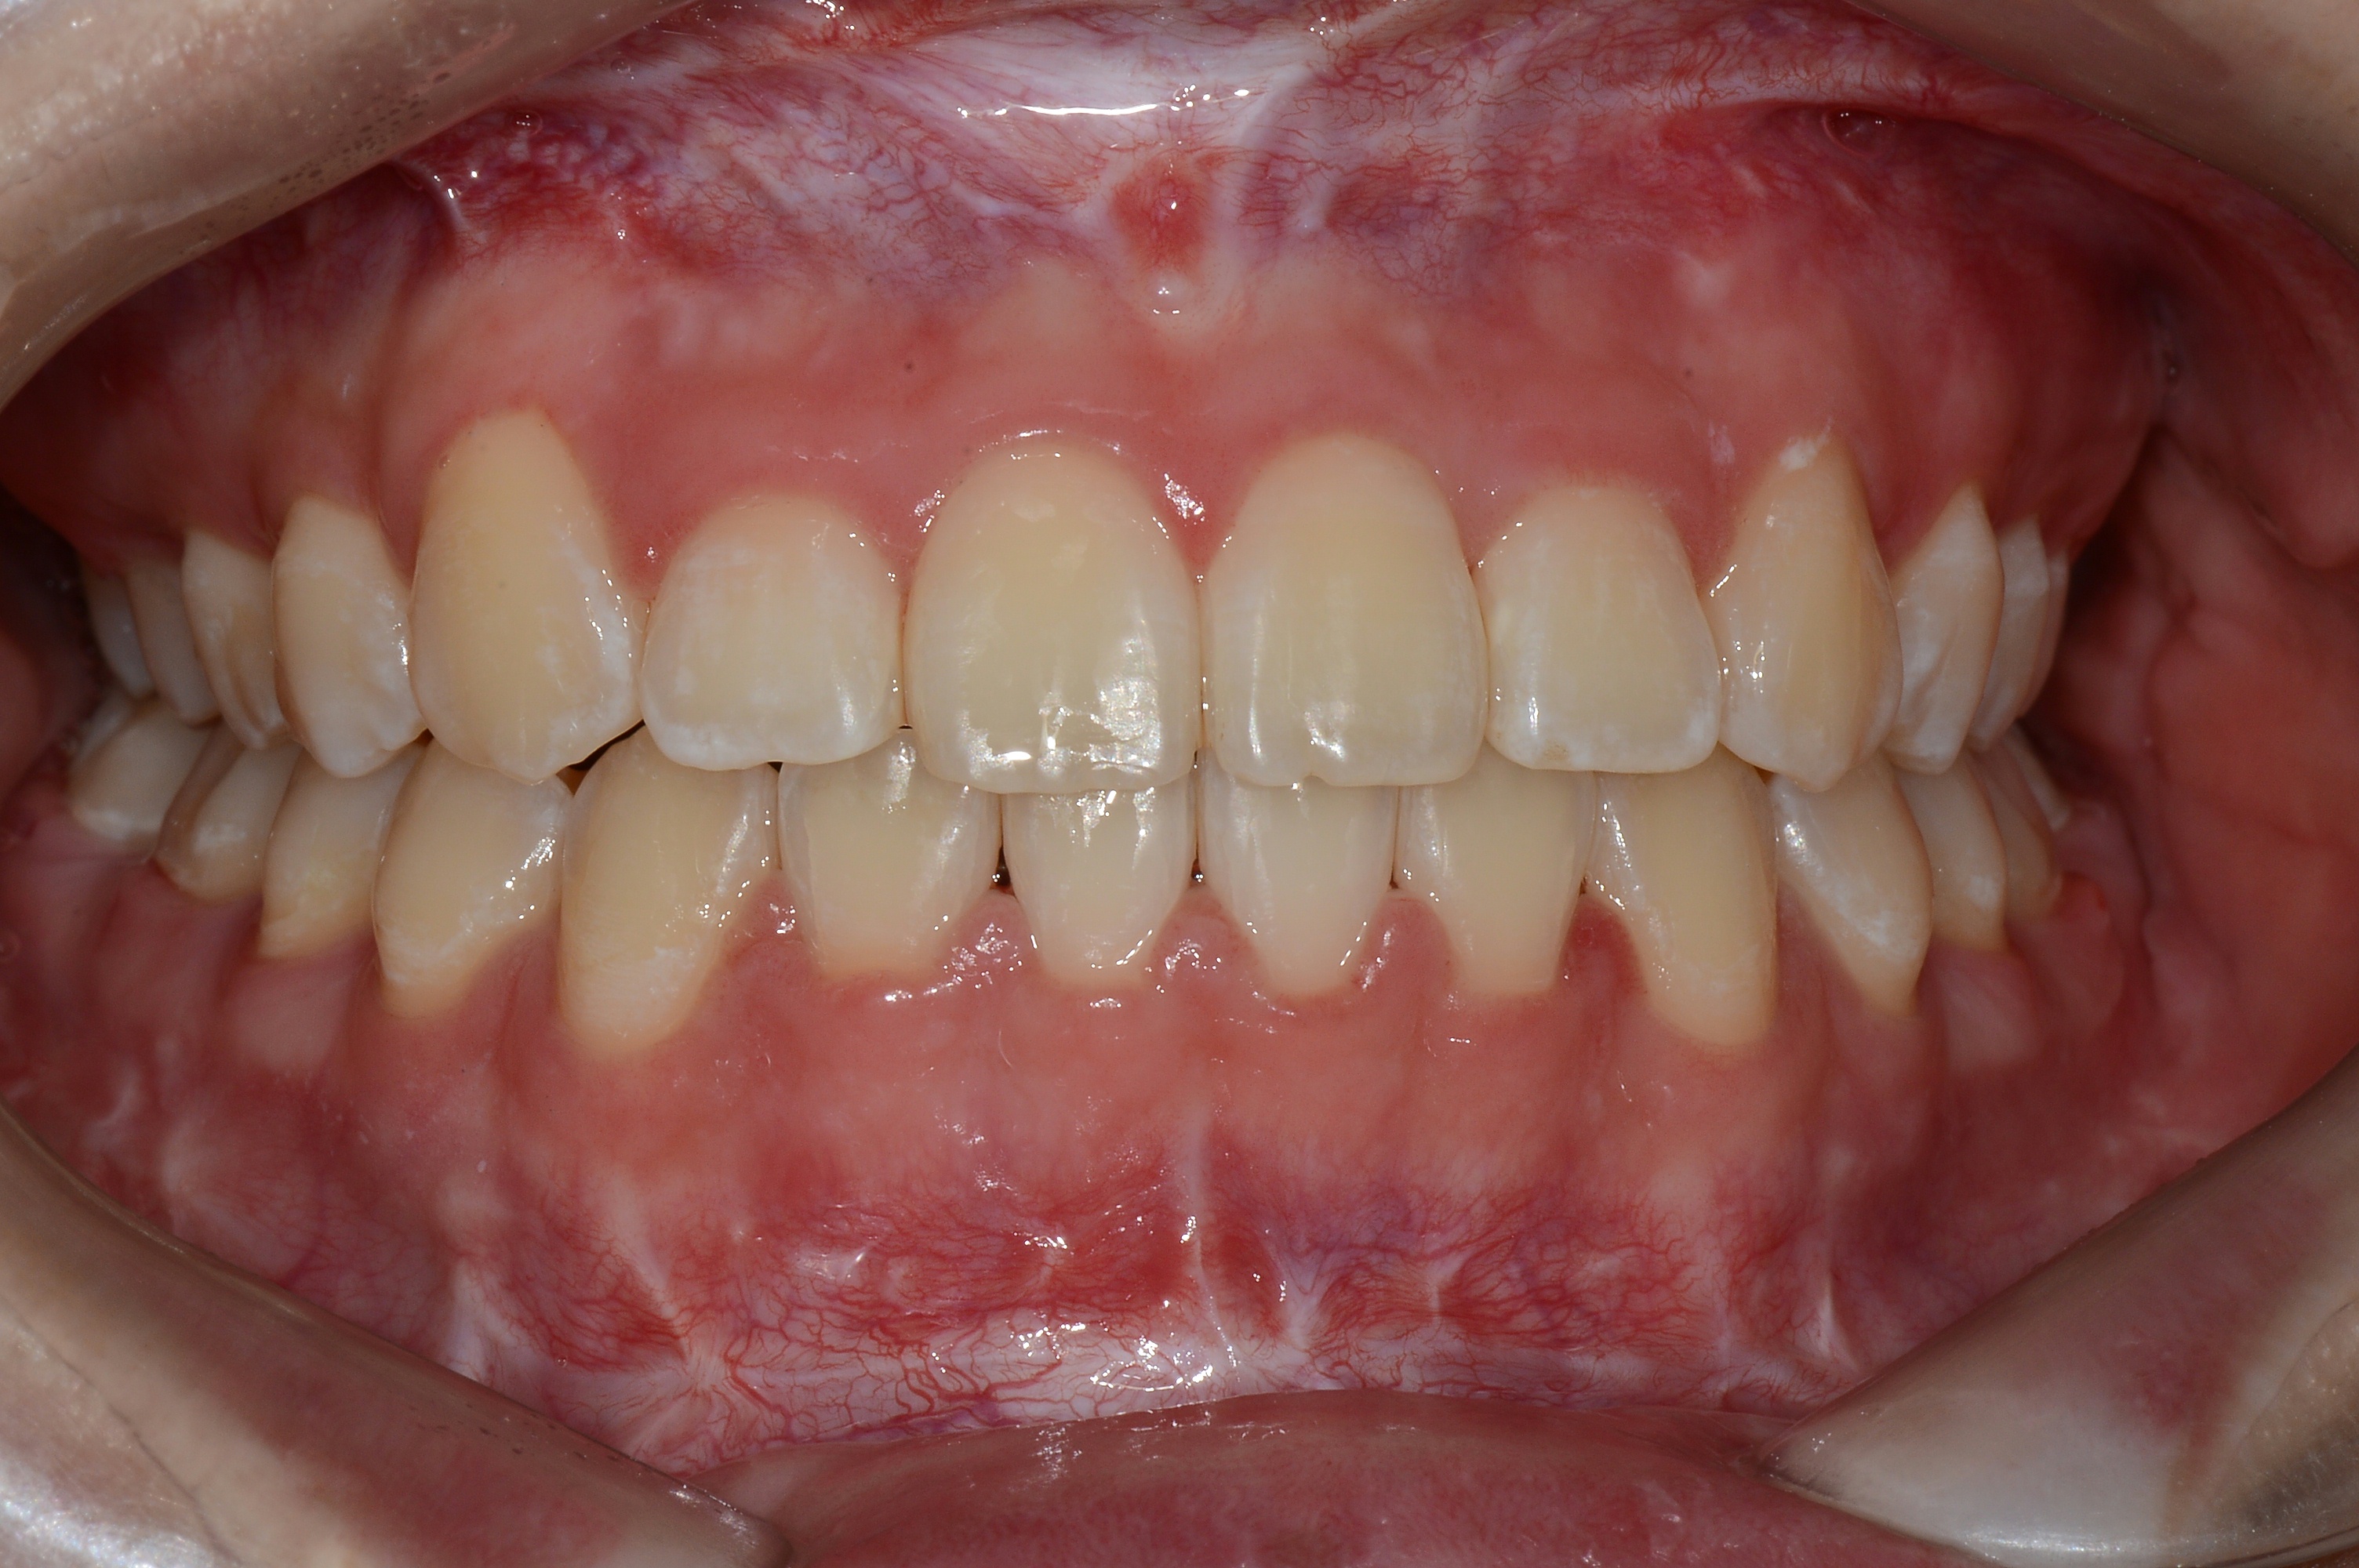

치료 전 사진입니다.